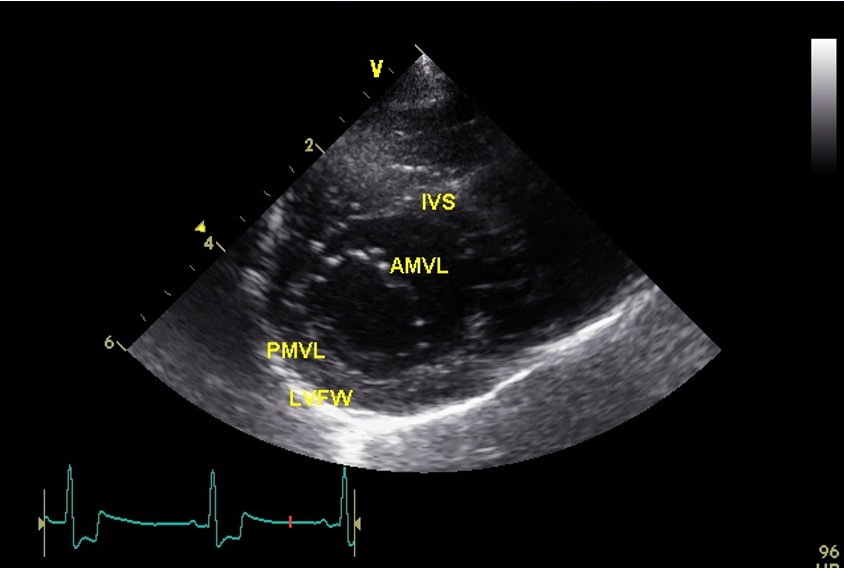

Which view is this?

Right parasternal short axis @ mitral valve